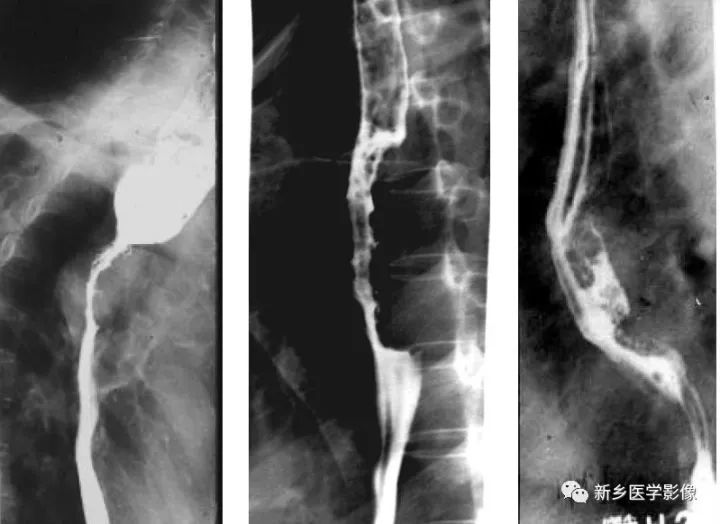

中晚期食管癌鋇餐造影圖像

a、浸潤(rùn)型食管癌,顯示食管上段向心性狹窄,邊緣不規(guī)則,局部見(jiàn)軟組織腫塊,狹窄以上食管擴(kuò)張

b、增生型食管癌,食管中段偏心性不規(guī)則充盈缺損,邊緣不規(guī)則

c、潰瘍性食管癌,食管中段偏心性腫塊,局部見(jiàn)腔內(nèi)龕影